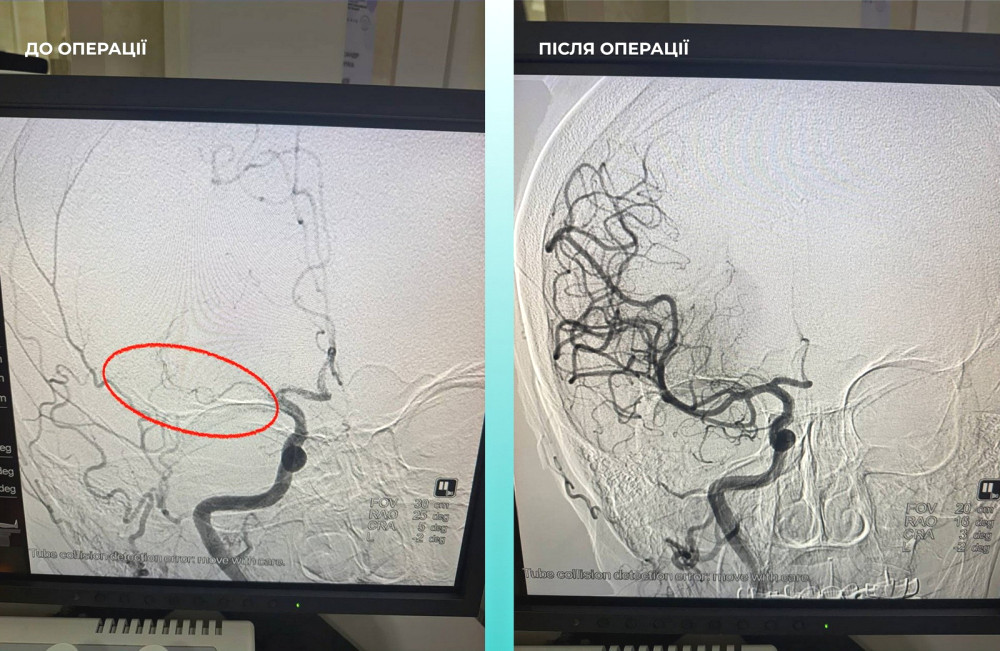

Пациентка, жительница Одессы, была госпитализирована в тяжелом состоянии с острым инсультом. При компьютерной томографии врачи обнаружили закрытие средней мозговой артерии.

Мультидисциплинарная команда врачей приняла сложное, но жизненно необходимое решение — провести одновременную тромбектонию на мозговой и легочной артериях.

Операция прошла успешно, и пациентка сейчас чувствует себя значительно лучше: она в сознании и уже начинает двигать конечностями.